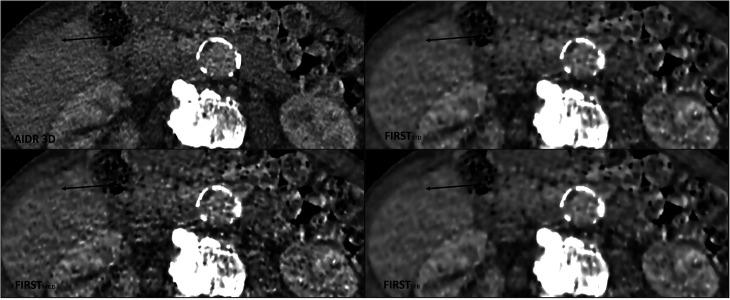

Patient images with reported poorly contrasted focal liver lesions were retrospectively reconstructed with the low-contrast attenuating algorithm (FIRST-LCD) from primary raw data. Liver-to-lesion contrast, signal-to-noise, and contrast-to-noise ratios for background and liver noise for each lesion were compared for all three FIRST-LCD presets with the established hybrid iterative reconstruction method (AIDR-3D). An additional visual conspicuity score was given by two experienced radiologists for each lesion.

A total of 82 lesions in 57 examinations were included in the analysis. All three FIRST-LCD algorithms provided statistically significant increases in liver-to-lesion contrast, with FIRST showing the largest increase (40.47 HU in AIDR-3D; 45.84 HU in FIRST;  < 0.001). Substantial improvement was shown in contrast-to-noise metrics. Visual analysis of the lesions shows decreased lesion visibility with all FIRST methods in comparison to AIDR-3D, with FIRST showing the closest results ( < 0.001).

回顾性地从原始数据中使用低对比度衰减算法(FIRST-LCD)对报告为对比度差的局灶性肝脏病变的患者图像进行重建。比较了所有三种 FIRST-LCD 预设与既定的混合迭代重建方法(AIDR-3D)的背景和肝脏噪声的肝病变对比度、信噪比和对比噪声比。两位有经验的放射科医生对每个病变的可视度进行了额外的评分。

共纳入 57 次检查中的 82 个病变进行分析。所有三种 FIRST-LCD 算法均显著提高了肝病变对比度,其中 FIRST 提高幅度最大(AIDR-3D 中为 40.47 HU,FIRST 中为 45.84 HU,P<0.001)。对比噪声指标也有显著改善。病变的视觉分析显示,与 AIDR-3D 相比,所有 FIRST 方法的病变可见度均降低,FIRST 结果最接近(P<0.001)。